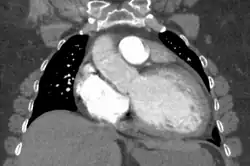

Generalized enlargement of the heart is seen upon normal chest X-ray. Pleural effusion may also be noticed, which is due to pulmonary venous hypertension.[28]

The electrocardiogram often shows sinus tachycardia or atrial fibrillation, ventricular arrhythmias, left atrial enlargement, and sometimes intraventricular conduction defects and low voltage. When left bundle-branch block (LBBB) is accompanied by right axis deviation (RAD), the rare combination is considered to be highly suggestive of dilated or congestive cardiomyopathy.[29][30] Echocardiogram shows left ventricular dilatation with normal or thinned walls and reduced ejection fraction. Cardiac catheterization and coronary angiography are often performed to exclude ischemic heart disease.[28]

Cardiac magnetic resonance imaging (cardiac MRI) may also provide helpful diagnostic information in patients with dilated cardiomyopathy.[32]